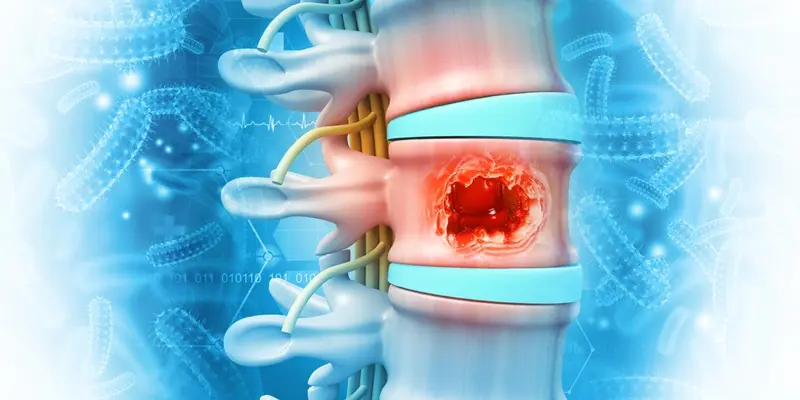

Tủy sống là một ống dây thần kinh dài khoảng 45 cm, nằm trong ống sống và được bảo vệ bởi các đốt sống. Nó đảm nhận vai trò truyền tín hiệu từ não bộ đến các cơ quan và ngược lại, điều khiển vận động, cảm giác, và một số chức năng tự chủ như hô hấp và tiêu hóa.

Một số nghiên cứu y học chỉ ra rằng tổn thương tủy sống có thể ảnh hưởng đến hầu hết các hoạt động sống hàng ngày. Vì vậy, bất kỳ khối u nào hình thành tại đây đều cần được nhận biết và xử lý kịp thời.

Tủy sống